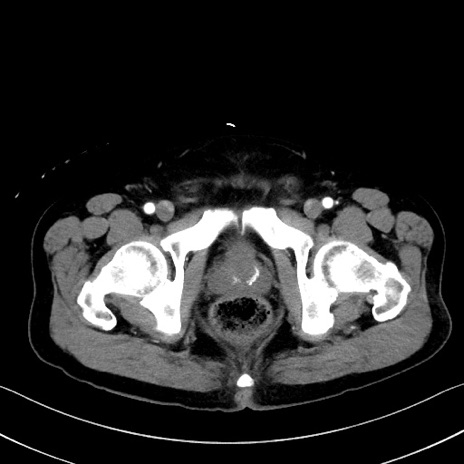

冠状断像

【症例】70歳代 男性

【主訴】腹部膨満、嘔吐

【現病歴】昨日より腹部膨満感出現。本日増悪し、仙痛出現。嘔吐あり、受診。

【既往歴】糖尿病、胆摘後

【身体所見】BP 149/80mmHg、HR 74/min、BT 35.9℃、腹部:膨満、軟、圧痛なし。腸雑音減弱あり。上腹部正中切開瘢痕あり。

【データ】WBC 13500、CRP 1.72